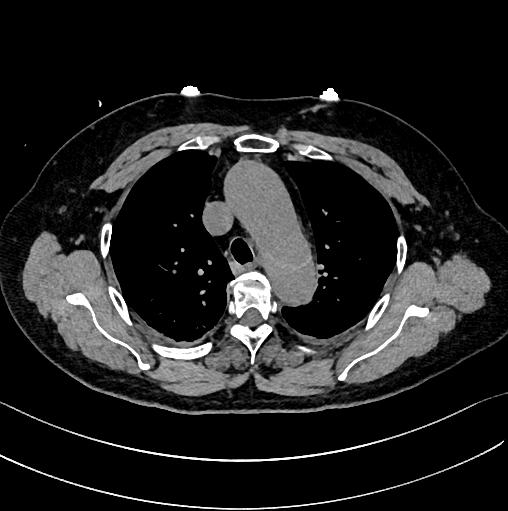

有些小伙伴开始着急了: 鲁迅你别说了,我们家的CT分辨率低,平扫绝对看不出动脉夹层!

下图的胸部CT平扫,有什么致命的问题?

图15

血管壁钙化啊,老年人很常见啊,能说明个锤子!

注意,看下面,钙化在血管的里面,不是在管壁!难道是血液钙化了?血液钙化?什么鬼?

图16

这不是血液钙化,这是主动脉夹层导致的血管钙化内移!血液不会钙化,因为动脉夹层,导致钙化的内膜被压迫进入血管!

增强CT一看,就一清二楚了!

图17